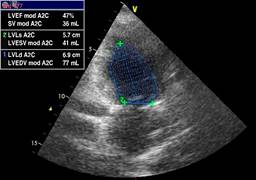

The initial LVEF was 36%, and 48 hours later, it was 47% (Figure 1). The echocardiogram showed important dilation of the left ventricle (Figure 2). The echocardiographic controls performed on the tenth day, at seven and 12 months, showed recovery and normal LVEF, demonstrating complete reversibility at 10 days that continues up to one year (Figure 3). There was no compromise in cardiac output according to measurements in the five echocardiograms performed. The cardiac index was calculated using the Dubois cardiac index estimation formula; the cardiac index was not altered during the development of the pathology.22 GLS is also used to assess left ventricular systolic function in patients with septic shock. It detects subtle changes in myocardial contractility and is more sensitive and accurate in evaluating systolic ventricular function compared to LVEF. We obtained a GLS of -14% initially (Figure 4); in the 12th month of echocardiographic control, normalization of the values was found with a GLS of -20.6% (Figure 5), therefore recovery of systolic function, which is considered normal at values of -18% to -20%. Measurement of variables through direct methods was not possible.

Figure 1: A two-chamber view showing the dilation of the left ventricle and the ejection fraction in the echocardiogram was performed 48 hours after the onset of the condition. LVEF = left ventricular ejection fraction. A2C = apical two-chamber (view). SV = stroke volume. LVLs = left ventricular length at end-systole. LVESV = left ventricular end-systole volume. LVLd = left ventricular length at end-diastole. LVEDV = left ventricular end-diastole volume.